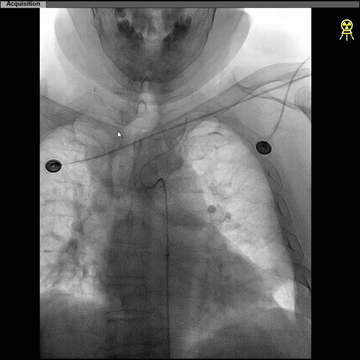

CTA:左ICA起始部重度狭窄,左CCA与无名动脉短共干,左CCA起始段走行明显向左,与主动脉弓呈显著锐角。

5F长椎管(125cm)+6F长鞘(90cm Cook)同轴,椎管头端旋调抵进共干开口,常规泥鳅导丝超选进入左CCA远端,因其近段与弓成角迂曲明显,导丝支撑不足,椎管尝试推进入左CCA失败。

更换125cm 5F预塑型西蒙管,在左锁骨下成形后,成功超选到左CCA。

西蒙管于左CCA造影,用硬泥鳅导丝超选入枕动脉,并西蒙管前推上高到枕动脉,加强上支撑,后长鞘顺利过弓,抵达左CCA远端。

建立治疗通路后,保护伞下(NAV6 4-7mm)行左侧ICA起始部狭窄支架植入(wallstent 9*40mm)。